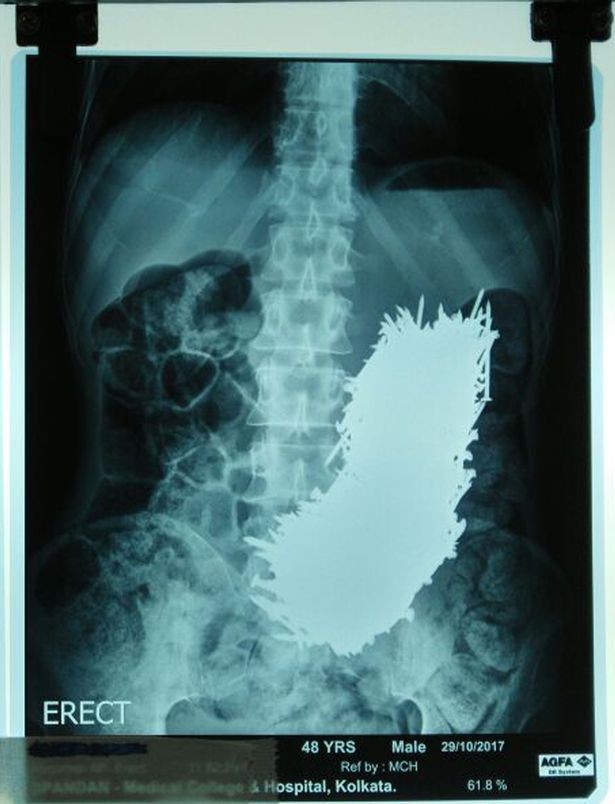

Ông Kumar được cấp cứu vào bệnh viện trong tình trạng đau bụng quằng quại. Sau khi nhìn kết quả siêu âm, cả bác sĩ lẫn nhân viên bệnh viện đều tá hỏa. Khoảng 600 chiếc đinh bằng thép nằm trong dạ dày.

Phim chụp siêu âm có phần... kinh dị của ông Kumar.

Tiến sĩ Siddhartha Biswas, người lãnh đạo đội ngũ y tế tại Đại học Y khoa và Bệnh viện Calcutta - Ấn Độ, nói: "Tôi là một bác sĩ khách mời tại phòng khám địa phương ở làng Dhali. Tháng trước, gia đình ông đã đưa bản báo cáo siêu âm cho chúng tôi, và tôi đã bị s.o^.c nặng khi tìm thấy 600 chiếc đinh thép trong bụng ông".

"Chúng tôi quyết định phẫu thuật cho anh ta. Có nguy cơ cao là bụng ông ta sẽ bị chướng và dạ dày bị đâm thủng do các đinh thép, nhưng may mắn thay điều đó đã không xảy ra".

"Chúng tôi cắt một phần dạ dày của Kumar và dùng một nam châm để hút từng chiếc đinh thép, mỗi chiếc một lần, trong đó có hơn 600 chiếc đinh thép. Chúng tôi làm hết sức cẩn thận để chắc chắn rằng tất cả đinh mà ông ấy đã nuốt đều phải được lấy ra".